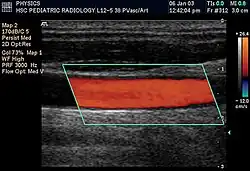

Duplex ultrasonography sometimes refers to Doppler ultrasonography or spectral Doppler ultrasonography.[3] Doppler ultrasonography consists of two components: brightness mode (B-mode) showing anatomy of the organs, and Doppler mode (showing blood flow) superimposed on the B-mode. Meanwhile, spectral Doppler ultrasonography consists of three components: B-mode, Doppler mode, and spectral waveform displayed at the lower half of the image. Therefore, "duplex ultrasonography" is a misnomer for spectral Doppler ultrasonography, and more exact name should be "triplex ultrasonography".[3]

Colour Doppler shows the direction of the blood flow in red or blue (either towards or away from the transducer). Meanwhile, spectral Doppler not only shows the direction of blood flow, it also shows the phases (pulsatility) and acceleration of the blood flow. Any sudden changes in direction of blood flow produces audible sounds on the ultrasound machine.[3]

In spectral Doppler, the y-axis shows the direction and velocity of the flow. Meanwhile, the x-axis (as known as "baseline") shows the flow over time. The gradient at any point on the waveform would therefore shows the acceleration of the flow. In "antegrade" flow, the blood flows according to the normal flow within the circulatory system (e.g. veins flow towards the heart while arteries flows away from the heart). In "retrograde" flow, the flow would reverse (e.g. veins flow away from heart or arteries flow towards the heart). However, "retrograde" flow can be both abnormal or normal. For example, in portal hypertension, there is an abnormal portal venous flow where it flows away from the liver (hepatofugal flow) instead of the normal flow towards liver (hepatopetal flow). In jugular venous pressure waveform of the internal jugular vein, the retrograde "a" waveform is a normal flow due to right atrium contraction. Both antegrade or retrograde flow can be either towards or away from the probe transducer, depending on the position of the probe relative to the blood flow. Blood flow toward the transducer would appear above the baseline while blood flows away from the transducer will appear below the baseline. Waveform of the flow can be classified as: pulsatile (as in arteries), phasic (as in veins), non-phasic (as in diseased veins), and aphasic (no flow). Spectral broadening (thickness of the waveform) increases from large vessels (plug flow) to medium vessels (laminar flow) to small/stenotic/diseased vessels (turbulent flow) due to a larger variety of blood with different ranges of velocities in those with turbulent flow.[3]